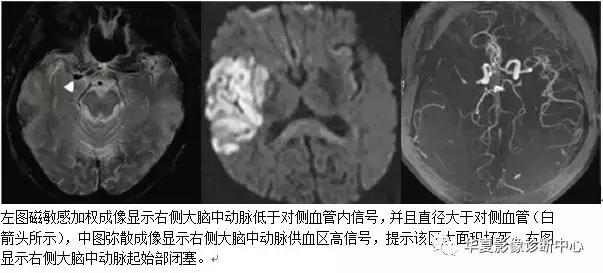

磁敏感加权成像(SWI) 也称作“高分辨率血氧水平依赖静脉成像表现为在T1加权梯度回波或灌注成像等基于磁敏感性的成像序列图像上,明显低信号的动脉直径超过对侧相应动脉的直径,以大脑中动脉或基底动脉较为常见。这种现象主要是由于颅内主要磁敏感改变与血液中铁的不同形式有关,含氧血红蛋白为反磁性物质,而脱氧血红蛋白、正铁血红蛋白和含铁血红素为顺磁性物质。静脉结构成像依赖于其内脱氧血红蛋白引起磁场的不均匀性导致的血管与周围组织的相位差加大。根据这个原理,急性期血栓中含有大量的脱氧血红蛋白,为红色血栓的主要成分,因此SWI 能够显示急性期血管内的血栓。

SWI 对大脑中动脉(MCA)近端闭塞(起始至发出豆纹动脉段) 有很好的显示作用。表现为血管内信号降低,能够显示出沿血管走行的血栓影像,并且 SWI 显示的血栓直径均大于对侧血管的直径,这可能是由于血管壁的完整性遭到破坏,血液成分从血管中向外渗出的结果。但是,当MCA 远端闭塞时形成的红色血栓体积较小,尤其是血栓发生在已经有动脉硬化的狭窄管腔中,部分容积效应可能使血栓影像被掩盖,因而可能出现假阴性。